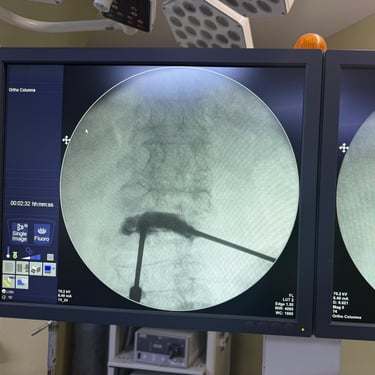

Fractura Lumbar Osteoporótica / Vertebroplastía y Bloqueo Lumbar Selectivo

La fractura lumbar osteoporótica y la artrosis lumbar son causas frecuentes de dolor crónico y limitación funcional en el adulto mayor. La osteoporosis debilita las vértebras, favoreciendo fracturas incluso ante esfuerzos mínimos, mientras que la artrosis genera desgaste articular e inflamación. La vertebroplastía percutánea permite estabilizar las vértebras fracturadas mediante la inyección de cemento óseo, proporcionando alivio rápido y mejorando la movilidad. En casos de dolor persistente por artrosis, el bloqueo lumbar selectivo ayuda a reducir la inflamación y el dolor. Ambas técnicas son procedimientos mínimamente invasivos que mejoran la calidad de vida y facilitan la recuperación funcional.